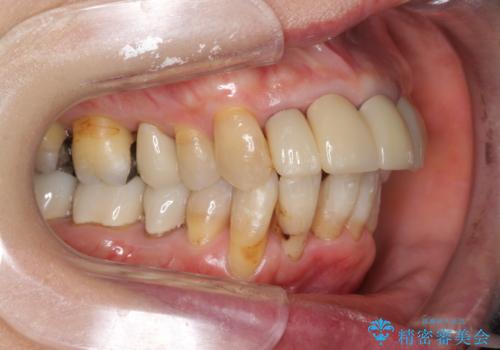

- 上顎前歯の黒ずみの改善、下顎前歯の十度なガタつき、矯正治療とセラミック治療を含む全体的な治療を希望され来院されました。

銀歯を高強度の仮歯に替えたのち、下顎前歯のみの部分矯正→全体的なマウスピース矯正治療(インビザライン)→最終的なセラミック治療と治療を進めます。

矯正治療と目立つ銀歯のやりかえを行ったことでかみあわせだけでなく、審美性・清掃性も改善し口腔内の環境を劇的に改善することができました。